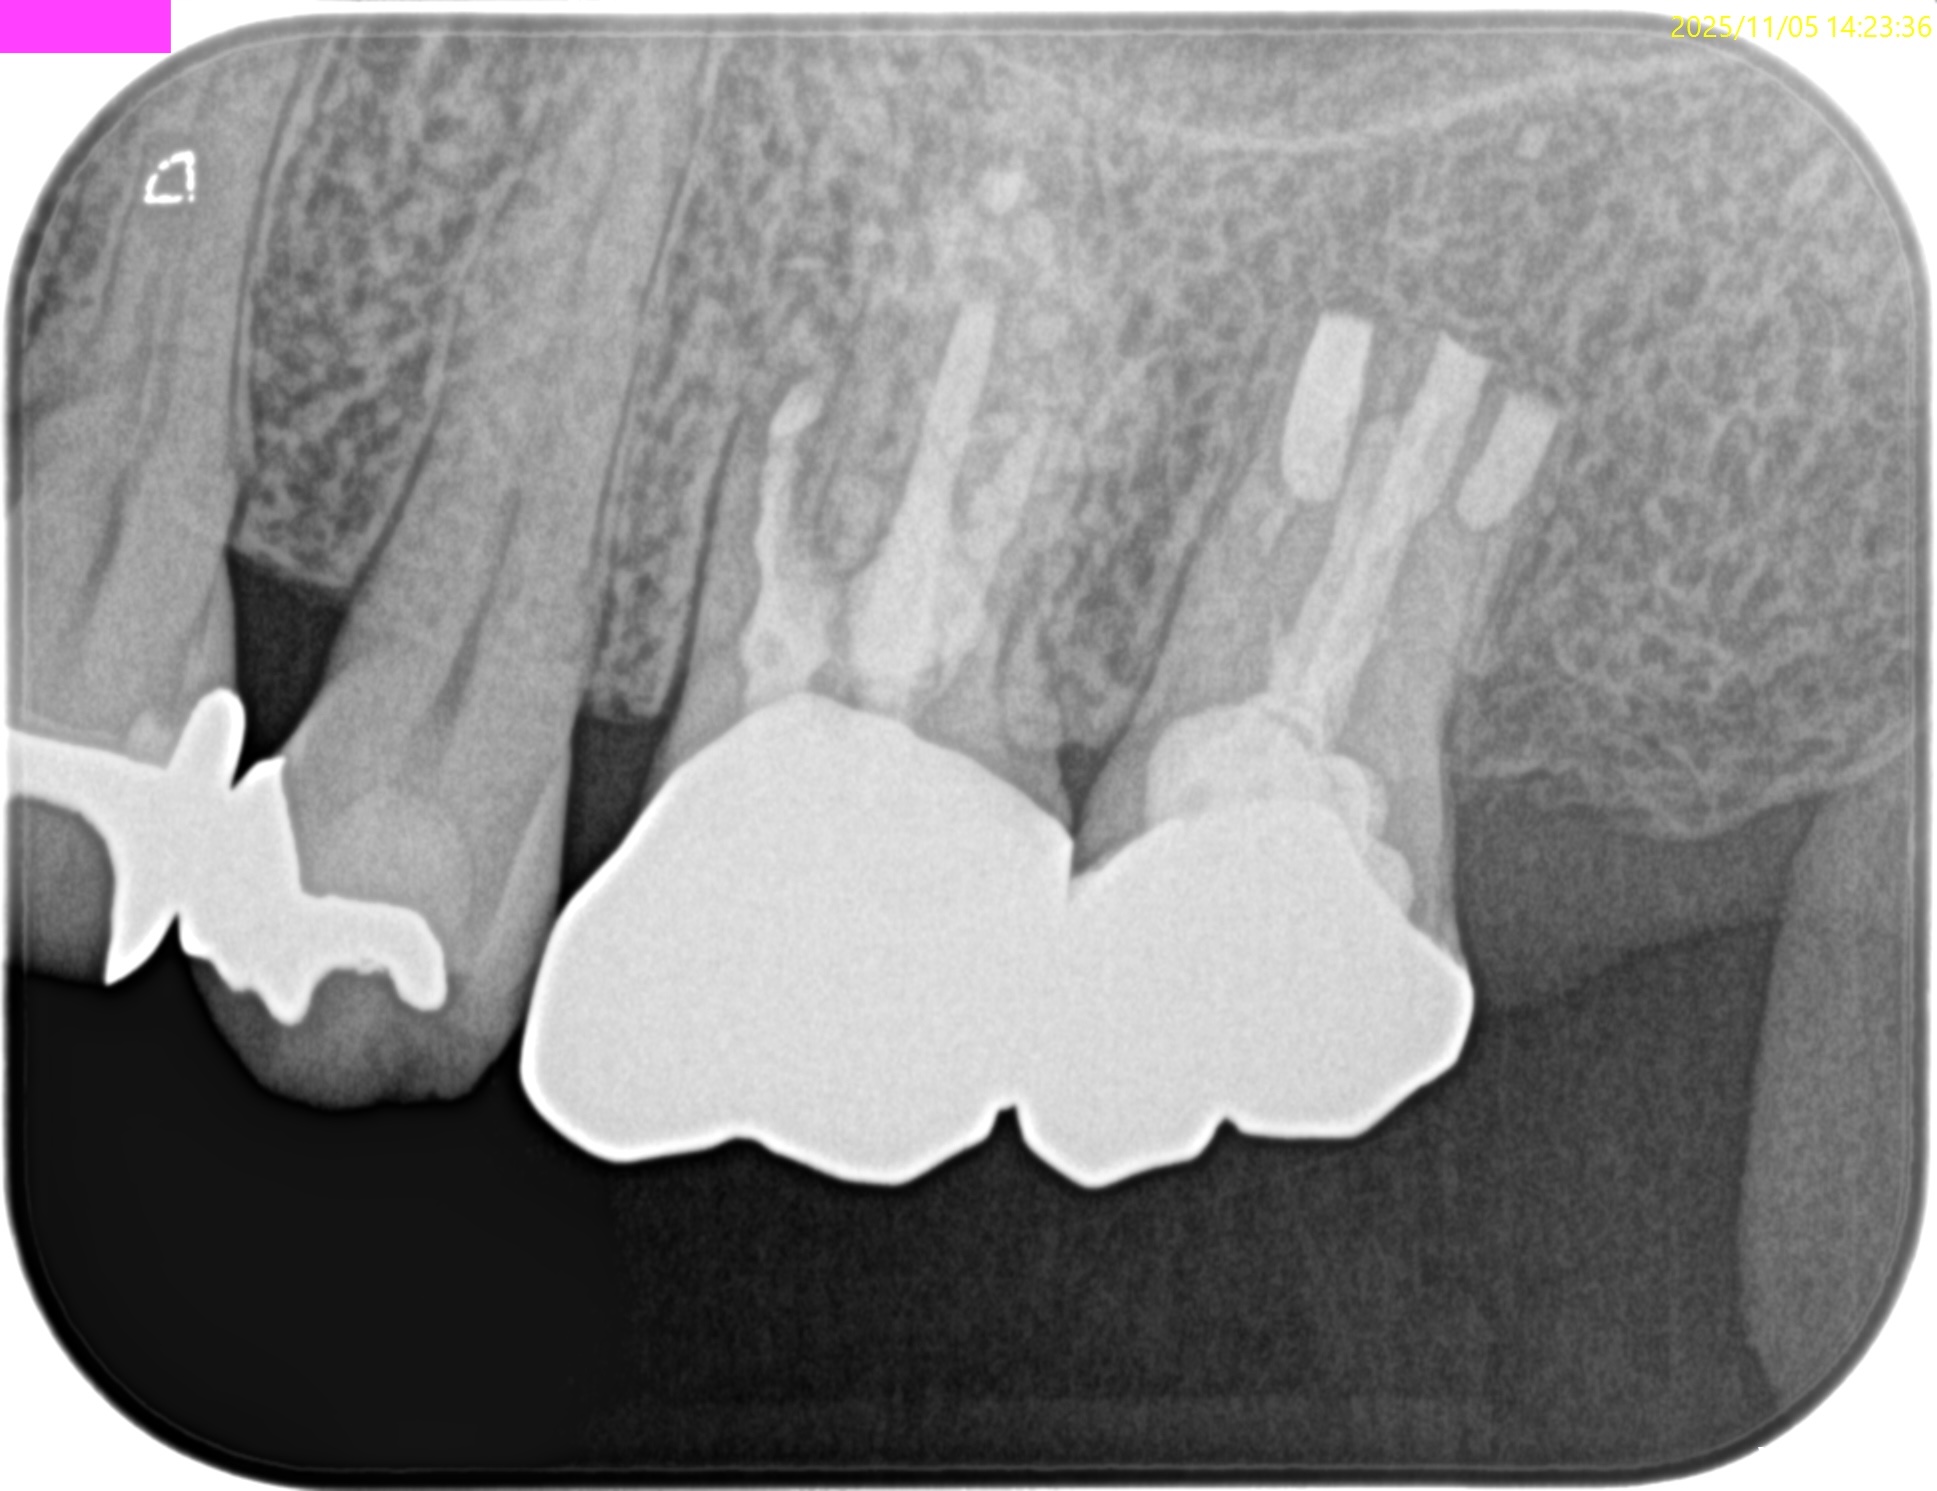

PA(2025.11.5)

治療前/直後と1年後を比較した。

完治だ。